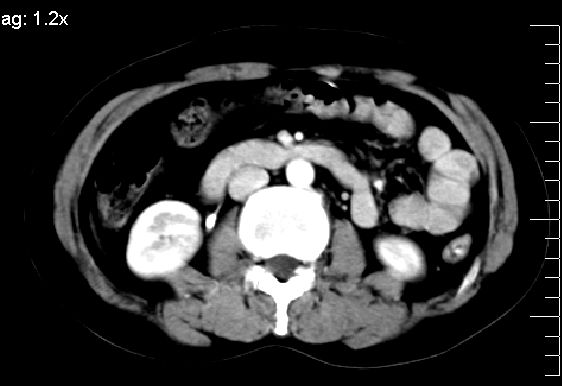

ct表现:

肝大小形态未见异常,肝内外胆管无扩张,肝s8段见一动脉期明显血管样强化结节,门脉期呈高密度,延迟期呈等密度,胆囊不大,增强扫描见胆囊及胆囊颈管壁增厚,有强化。

双肾灌注良好,代谢增快,动脉期肾盂见造影剂,左肾下极背侧见一略低密度病灶,延迟期见似不强化囊肿,双侧肾上腺未见异常。

胰腺及脾未见异常。肾门水平腹膜后见小淋巴结。腹腔未见积液征象。

诊断:

1、胆囊炎(轻度)。

2、肝s8段结节,考虑小血管瘤。

3、左肾下极低密度灶,考虑囊肿可能性大,建议随访,除外小肾癌(无强化可以基本除外)。

4、目前ct表现尚不能解释患者上腹部疼痛,建议上消造影检查,除外胃炎等疾患。